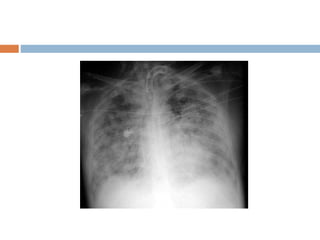

Pulmonary Edema (intertitial)

There are two basic types of pulmonary edema:

 Cardiogenic pulmonary edema caused by

increased pulmonary capillary pressure

 Noncardiogenicpulmonary edema caused by

either altered capillary membrane permeability

or decreased plasma oncotic pressure

Pulmonary edema

Interstitial disease

 Ground glass appearance